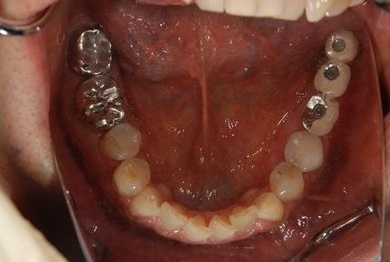

| 性別/年齢 | 男性 / 69歳 | ||||||||||||||||||||||||||||||||

| 主訴 | 1.左上奥歯の詰め物が取れた 2.左上前歯の欠け 3.右下奥歯の欠け | ||||||||||||||||||||||||||||||||

| 治療方針 | セラミック治療にて、審美的回復を行う。 | ||||||||||||||||||||||||||||||||

| 治療内容 | メタルボンドセラミッククラウン1本(メタルボンド用土台1本)、ハイブリッドセラミックインレー1本 | ||||||||||||||||||||||||||||||||

| 総治療費 | 172,410円 | ||||||||||||||||||||||||||||||||

| 治療期間 | 4ヶ月 |